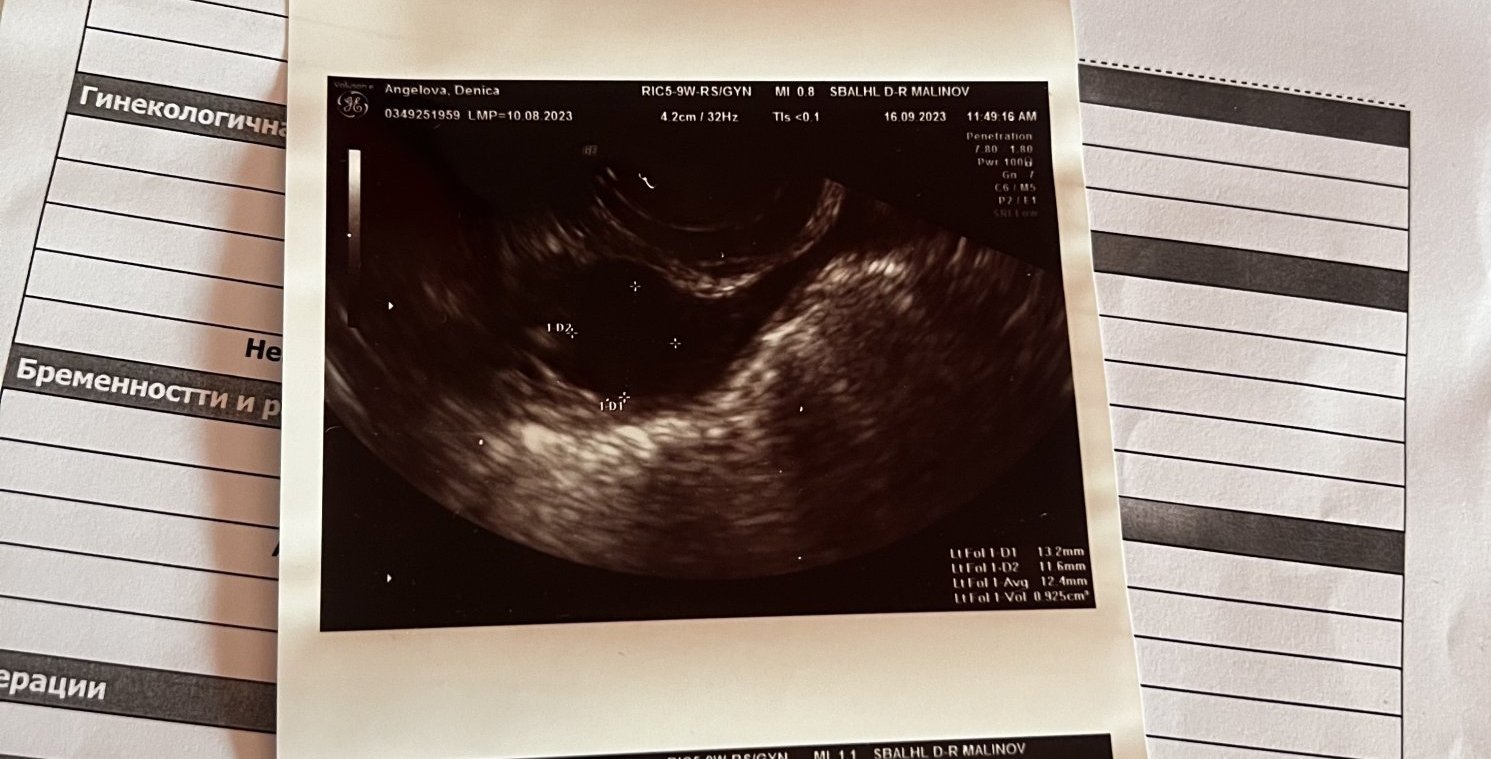

Мнение за снимката за 7 дни закъснение с нередовен съм?